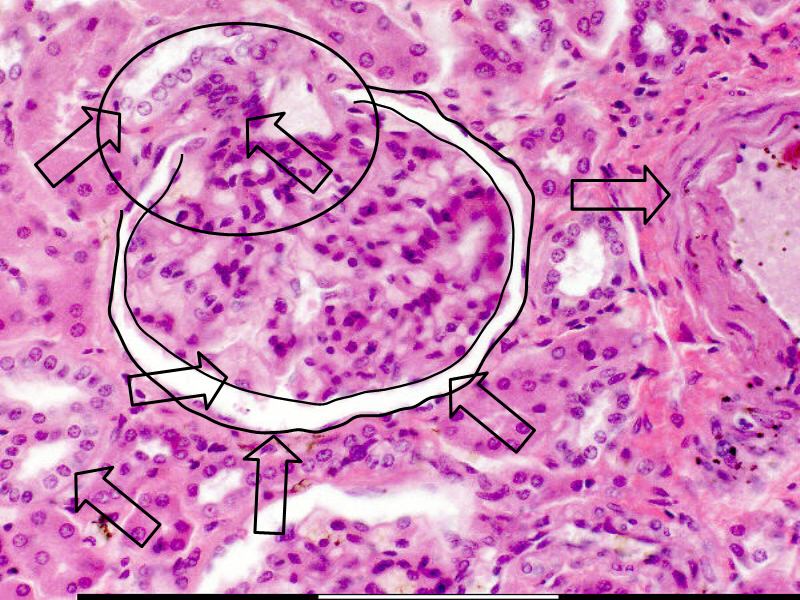

Kidney

- Make a line diagram, using supplied labels.

- Label the colour slides.

- Annotate the two diagrams

- Complete the diagram:

- Events in each part of the nephron

- Stimulate / Inhibit

Go with the flow